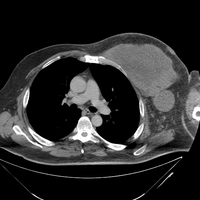

DLBCL/DHL-CT Chest 2

CT chest of a patient with refractory double hit lymphoma showing a very large mass in the superoanterior aspect of the left chest wall extending into the neck (not shown). There was associated necrosis or infection within this mass with probable invasion of the left internal carotid artery and left subclavian artery with possible invasion into the left lobe of the thyroid gland.